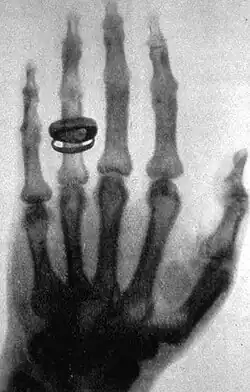

Em um determinado momento, enquanto investigava a capacidade de vários materiais de deter os raios, Wilhelm colocou um pequeno pedaço de chumbo em posição enquanto a descarga acontecia. Wilhelm viu então a primeira imagem radiográfica, seu próprio esqueleto cintilando na tela de platinocianeto de bário. Mais tarde, ele relatou que foi nesse ponto que decidiu continuar seus experimentos em sigilo, porque temia por sua reputação profissional se suas observações estivessem erradas.[5][6]

O artigo original de Wilhelm, Ueber Eine Neue Art von Strahlen ("Sobre uma nova espécie de Raios"), foi publicado 50 dias depois, em 28 de dezembro de 1895.[12] Em 5 de janeiro de 1896, um jornal austríaco relatou a descoberta, por Wilhelm, de um novo tipo de radiação. Após a descoberta dos raios-X, Wilhelm recebeu o título de Doutor Honorário em Medicina, da Universidade de Würzburgo. Entre 1895 e 1897, ele publicou três artigos a respeito dos raios-X, cuja tradução para o português pode ser vista nos links externos. Até os dias atuais, nenhuma das suas conclusões foi considerada falsa. Atualmente, Wilhelm Röntgen é considerado o pai da Radiologia de Diagnóstico – a especialidade médica que utiliza imagem para o diagnóstico de doenças.[3][6]